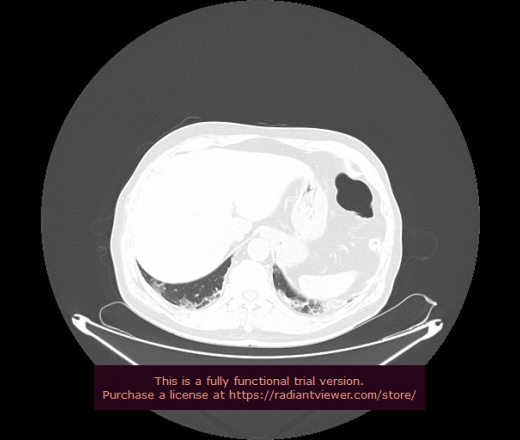

Уважаемые коллеги, если имеется интерес, сможете ли Вы спрогнозировать дальнейшее +-одинаковое течение процесса у 4 данных разных пациентов? Зацепиться где-то можно очень просто, где-то нельзя.